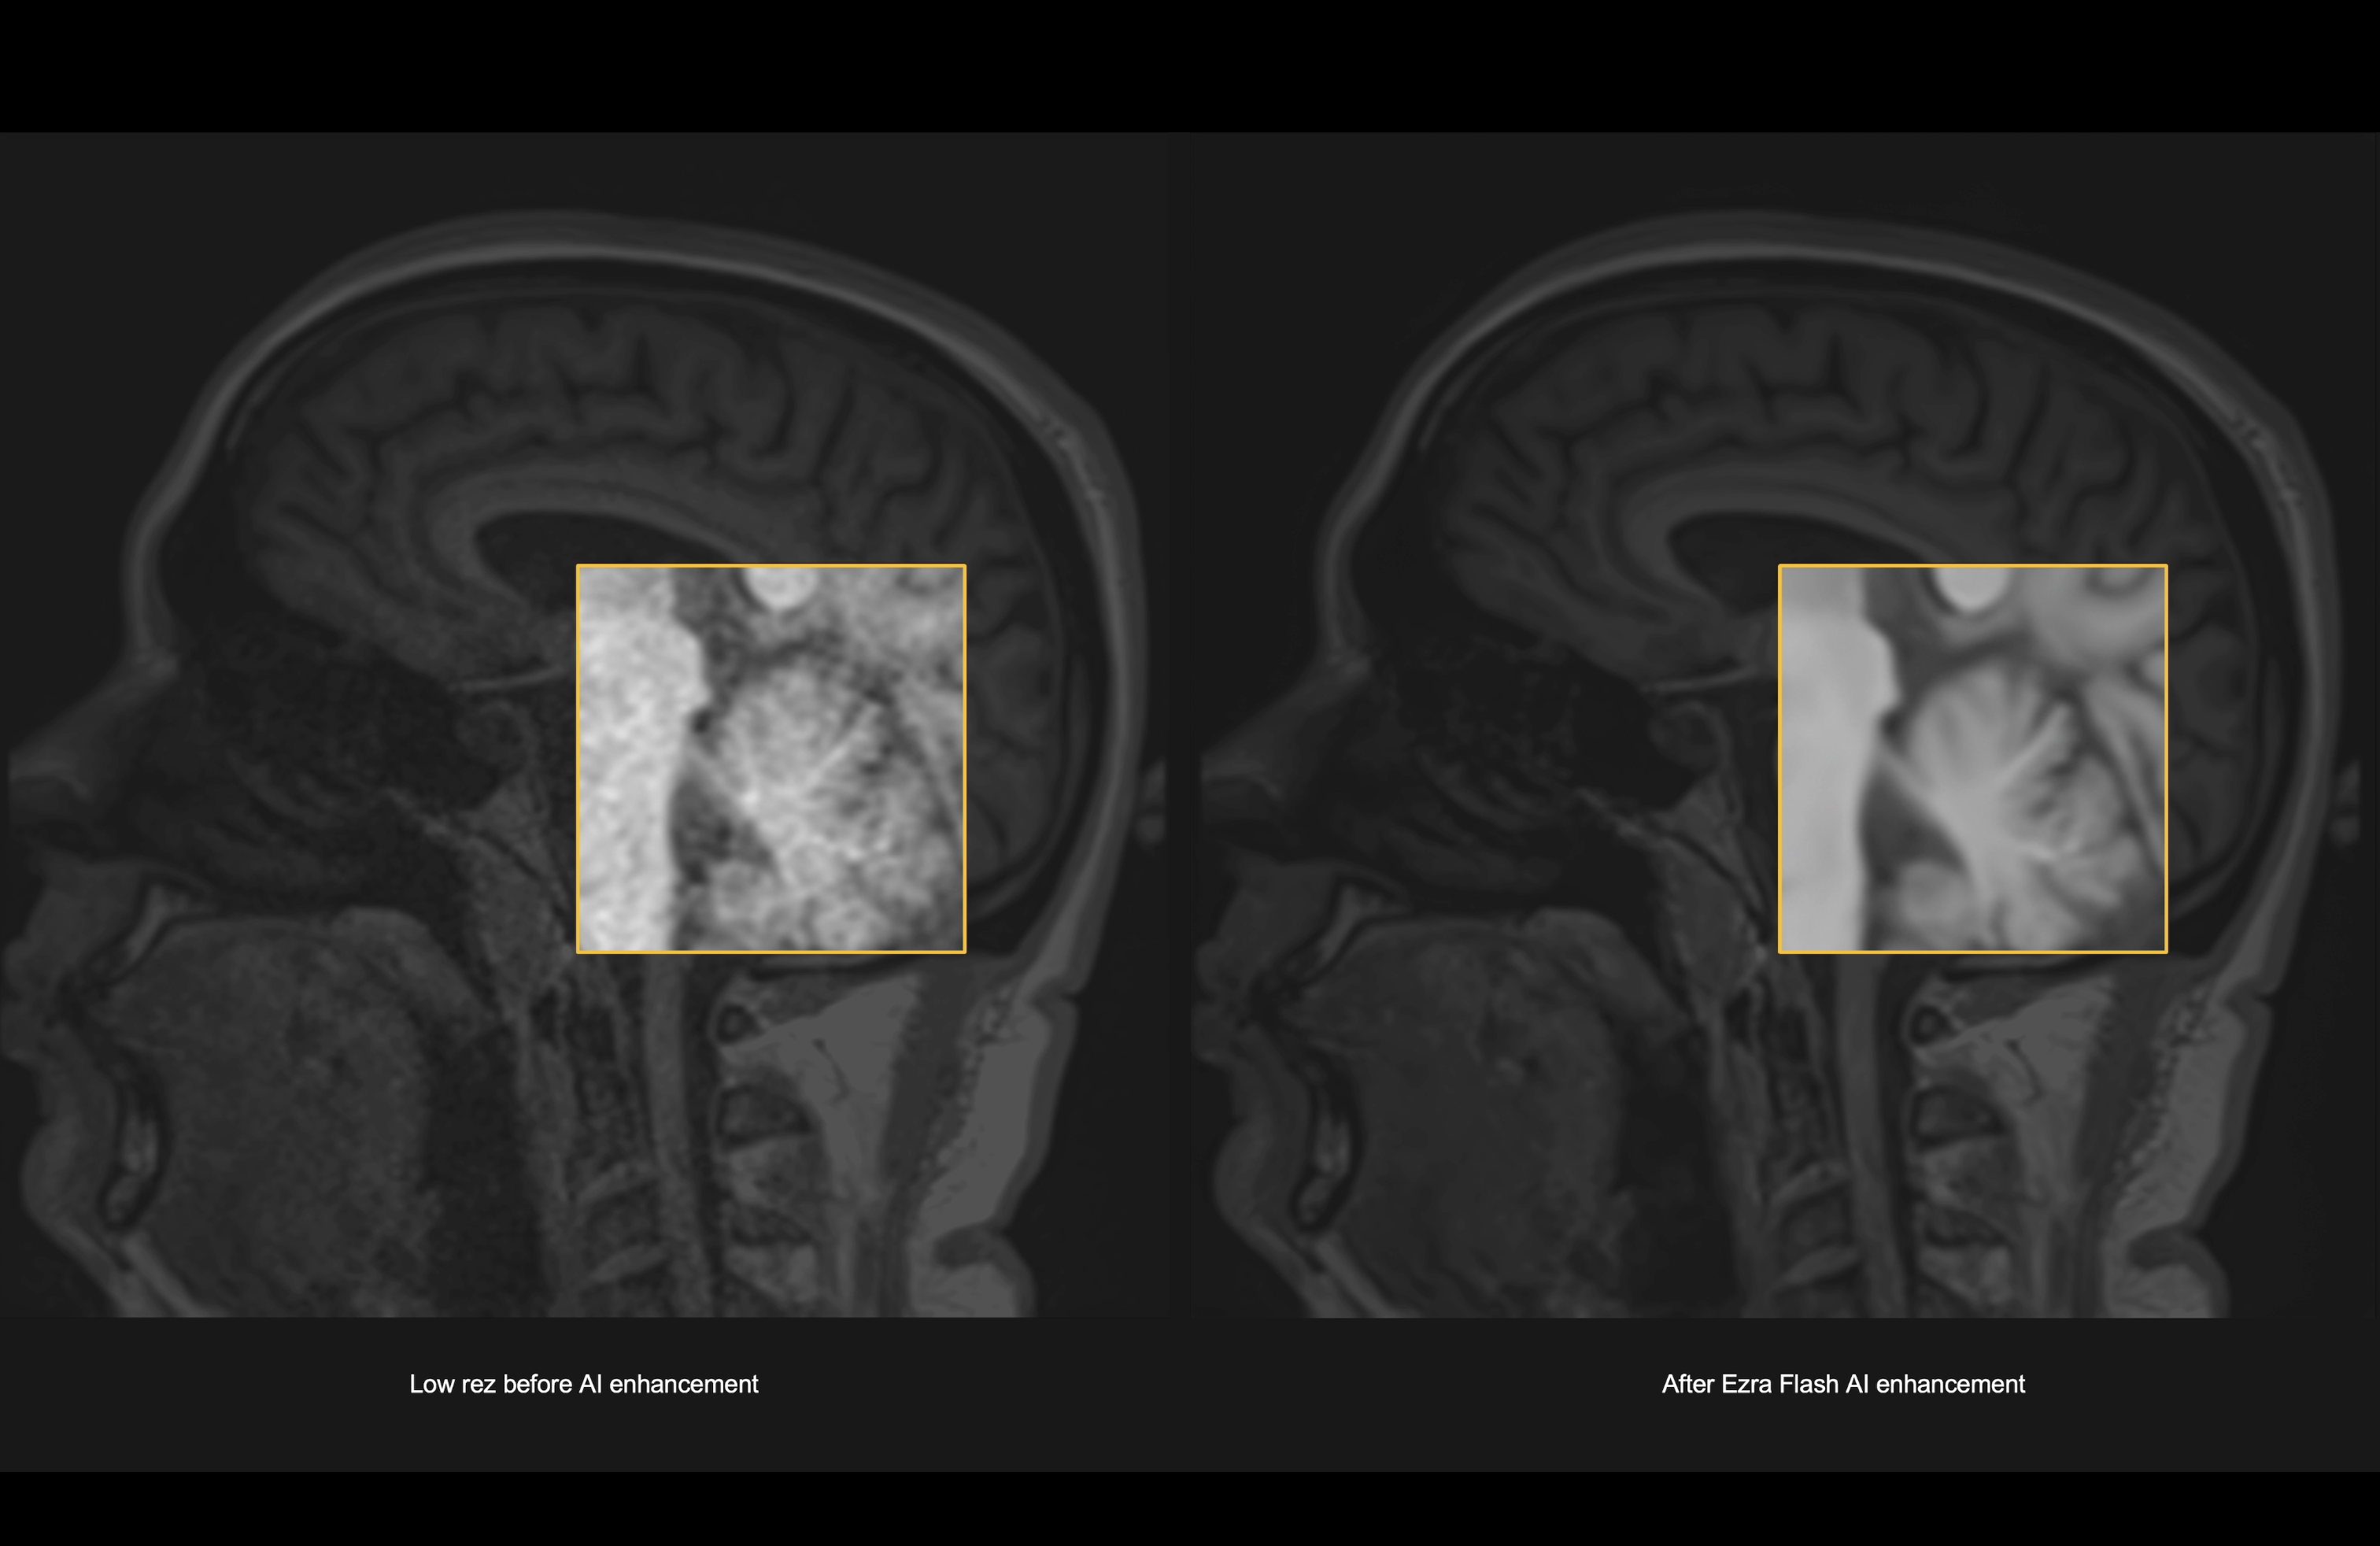

Today, I’m incredibly excited to announce that we have received 510(k) FDA clearance for the Ezra Flash AI, enabling us to roll out the world’s first 30-minute full body MRI. The new AI reduces noise and improves the quality of MRI images, enabling us to create a scanning protocol with twice the speed and same image quality.